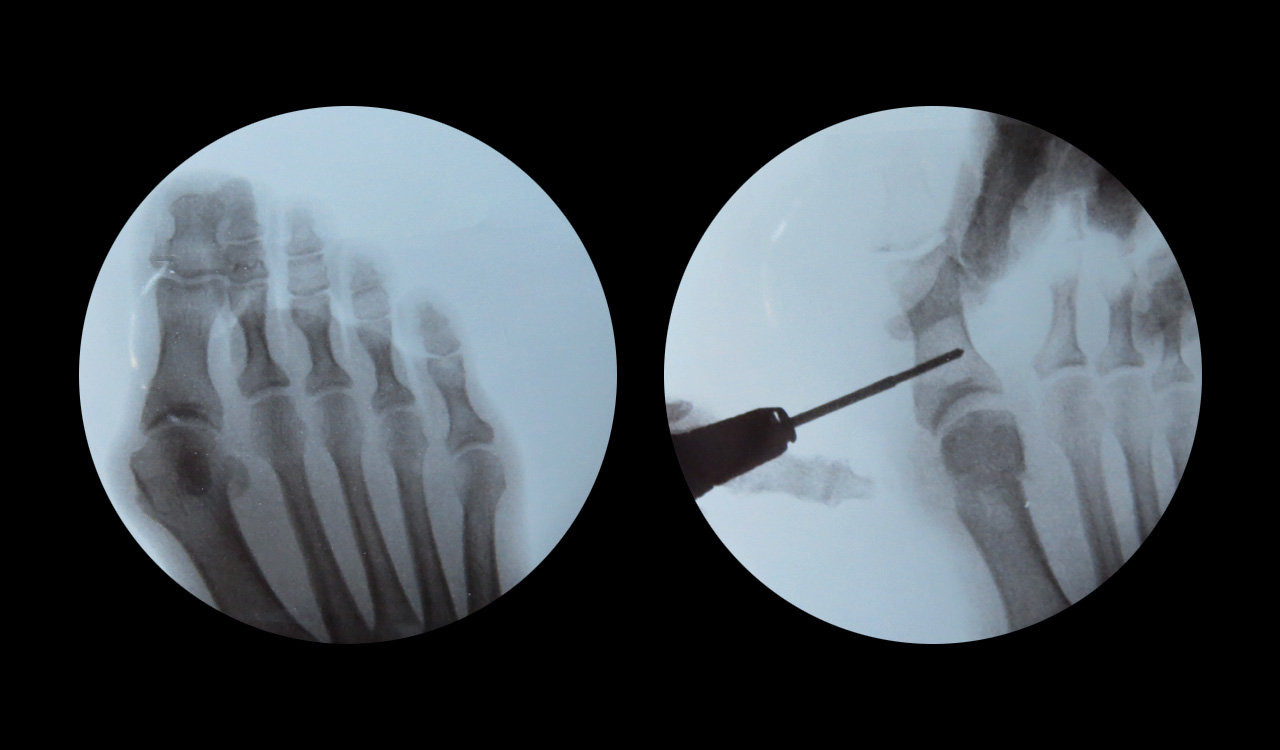

Tras haber descartado posibles tratamientos conservadores, se planteará como tratamiento definitivo una intervención mínimamente invasiva para corregir el juanete.

Las ventajas de este tipo de intervención sería que el paciente está en todo momento consciente y se marcha andando a casa por su propio pie, además el hecho de realizar mini-incisiones y no utilizar materiales de osteosíntesis (tornillos, agujas) reduce los tiempos de recuperación y disminuye las probabilidades de infección.

Para obtener un buen diagnóstico, se llevará a cabo un estudio radiológico del antepié y un estudio biomecánico de la marcha, además de observar los diferentes síntomas presentes y morfología del pie.

En función del grado de deformidad, se planteará el tratamiento más adecuado para cada caso, desde tratamientos conservadores hasta tratamientos definitivos con Cirugía de Mínima Invasión del Pie.